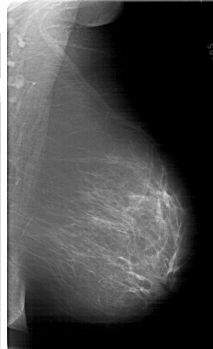

A_1719_1.RIGHT_MLO

RIGHT_CC LINES 6676 PIXELS_PER_LINE 3826 BITS_PER_PIXEL 12 RESOLUTION 43.5 NON_OVERLAY

RIGHT_MLO LINES 6616 PIXELS_PER_LINE 4036 BITS_PER_PIXEL 12 RESOLUTION 43.5 NON_OVERLAY